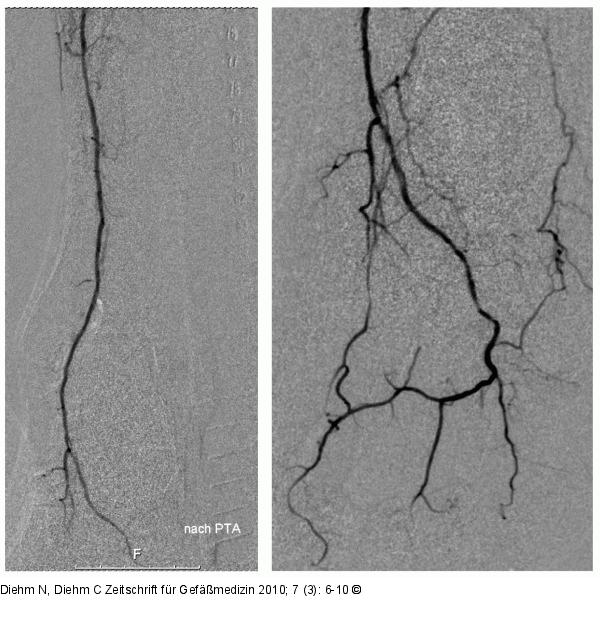

Abbildung 3: Distaler Unterschenkel Angiographisches Abschlussergebnis am distalen Unterschenkel (links) und Fuß (rechts). |

Abbildung 3: Distaler Unterschenkel

Angiographisches Abschlussergebnis am distalen Unterschenkel (links) und Fuß (rechts). |